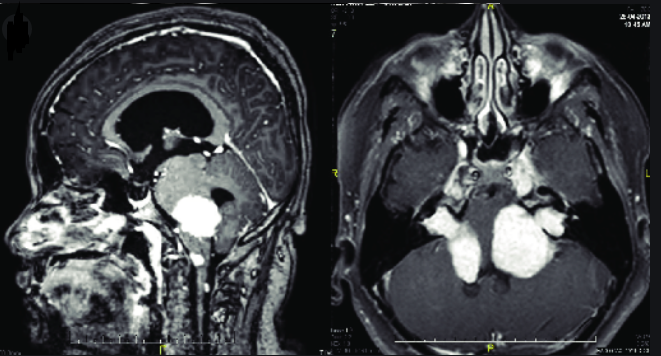

在具有遗传风险的肿瘤中,在某些情况下,神经鞘瘤是由遗传病引起的。在神经鞘瘤中,三叉神经鞘瘤是比较常见的类型,是二常见的神经鞘瘤,仅次于常见的听神经鞘瘤。三叉神经鞘瘤是一种发生于颅底、起源于雪旺细胞的颅内外周神经鞘瘤。雪旺细胞是一种胶质细胞,帮助保护周围神经系统神经元传递信息和指令。这些细胞通过在神经细胞周围形成一层叫做髓鞘的保护层来做到这一点。那么,三叉神经鞘瘤会遗传吗?

对此,James T.Rutka教授表示,大多数神经鞘瘤不是遗传性的。多数是偶然发生的,并且是单一的肿瘤。在某些情况下,由于潜在的遗传疾病如神经纤维瘤病2(NF2)、神经纤维瘤病或卡尼综合征,患者会发展成神经鞘瘤(或多发性神经鞘瘤)。这些疾病以常染色体显性遗传。这意味着在每个细胞中只有一个负责基因的拷贝发生变化(突变)就足以导致这种情况的特征。虽然神经鞘瘤可能是由遗传病引起的,但三叉神经鞘瘤本身是不会遗传的,三叉神经鞘瘤是良性的,它们生长缓慢。虽然它们不会侵入大脑,但当它们的体积增大时,会对大脑造成压力。当肿瘤变大时,也会伤害其他神经。